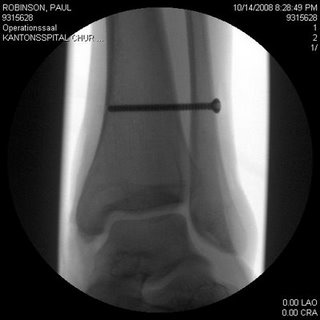

Paul Robinson předčasně ukončil svůl 3,5 měsíční trip po evropských bouldrových oblastech. Přiměla ho k tomu zlomená holení kost a přetrhané vazy v kotníku jeho levé nohy. Tuhle "radost" si přivodil 14.10. pádem z téměř vylezeného boulderu Unendliche Geschichte (1+2) na Bruno bloc v Magic Woodu. Pokus předtím spadl ve stejném místě na konci dvojky, když mu smekla pata. Sám nevěděl proč a tak dal 20min pauzu, znovu nastoupil, přelezl klíč a v tom samém místě mu i přes pocit nadhledu opět smeklo. Jenže tentokrát ho to hodilo nečekaně do rotace a dopadl nalevou nohu... Na několik měsíců má teď od lezení útrum (zlomenina se neobešla bez šroubů v kosti), nicméně plánuje začít bušit na kampusu, protože prej nikdy nebyl vyloženě silnej lezec :-) Jeho cíl je být zpátky do Amerických národních závodů v únoru...tak ať mu to vyjde.